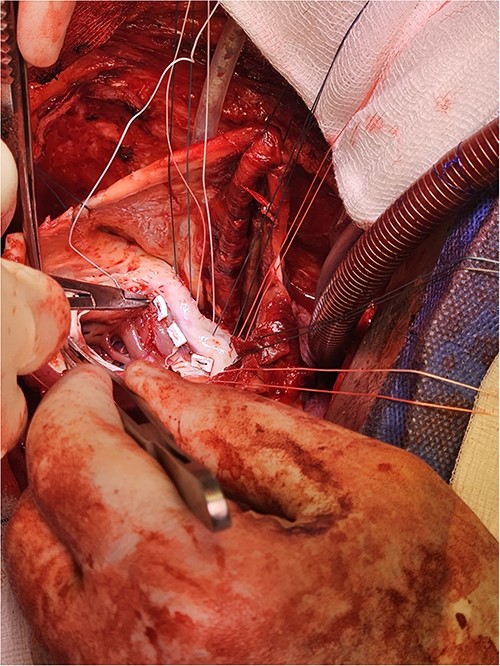

Following median sternotomy, cardiopulmonary bypass was instituted (bicaval drainage, ascending aortic return). Antegrade cardioplegia was delivered with aortic root venting and bicaval snaring. Dense adhesions surrounded the aneurysm, which had a thin wall, measured ⁓15 cm from LV apex to mitral annulus, and contained around 150 g of clot. The posterior mitral leaflet appeared retracted, preventing coaptation due to LV stretching. The aneurysm was resected (Fig. 2), and the LV wall repaired with a 5 × 3 cm patch, restoring normal LV size (Fig. 3). The musculotendinous junctions of the anterior and posterior papillary muscles were approximated using pledgeted 3–0 polypropylene sutures (Fig. 4). The patch repair was completed (Fig. 5), and the overlying sac oversewn for haemostasis.

Pledgeted Ethibond sutures were placed circumferentially around the aneurysm mouth.

Once the sutures for the patch were placed, the two papillary muscles were identified and another pledgeted suture through the musculotendinous junction was used to approximate them.